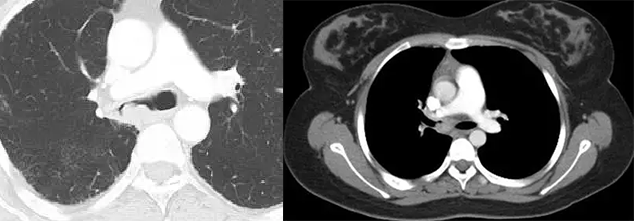

肉瘤样癌并肿瘤性动脉栓塞、自发性气胸。

两图分别为直肠癌支气管内膜转移、软骨肉瘤支气管内膜转移。